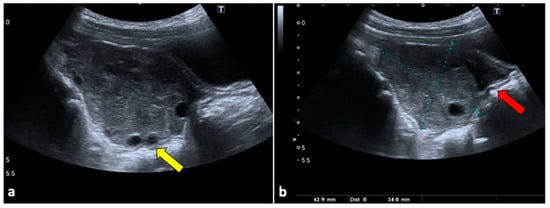

Although CT is not indicated as a first-line technique when OT is suspected, it is usually performed in female patients with aching nonspecific pelvic pain and vomiting. Moreover, it can be helpful for ruling out OT if US does not show ovarian abnormalities or if it is limited due to patient pain. CT scans usually show a large pelvic mass abnormally located at the midline, anteriorly to the uterus. During no-contrast scans, the ovary may appear hyperdense (>50 Hounsfield Unit) due to internal haemorrhage. In contrast-enhanced images, the ovarian twisted pedicle may be detected [27,28]. It can also be seen as a triangular enhancing soft tissue between the uterus and the involved ovary. Peripherally displaced follicles, fat stranding near the adnexa, and a small amount of free fluid are also common findings (Figure 2) [26].

Figure 2.

Left ovarian torsion in a 12-year-old woman with acute lower abdominal pain and vomiting. Axial (a), sagittal (b), and coronal (c,d) contrast-enhanced CT images show enlarged and oedematous left adnexa migrated to the midline and anteriorly to the uterus (yellow arrows), with peripherally displaced ovarian follicles. A small amount of free pelvic fluid (blue arrows) is associated. On the coronal plane, the twisted and oedematous ovarian vascular pedicle (red arrow) can be easily detected.

MRI is usually not available in emergency settings. However, it can be useful for further evaluating equivocal findings seen with other techniques and for characterising an underlying ovarian mass [26]. If haemorrhagic infarction is present, the involved ovary shows a T1 hyperintense signal during MRI, with low or without contrast enhancement, and can show diffusion restriction on Diffusion-Weighted Imaging (DWI) sequences. A T1 thin hyperintense ring, representing methaemoglobin, may also be present. Furthermore, the oedematous twisted pedicle can be seen as a heterogeneous structure with a high T2 signal located between the uterus and the enlarged ovary (Figure 3) [28,29].

Figure 3.

Left ovarian torsion in a thirty-nine-year-old patient with acute pelvic pain. Axial T2-weighted (a) and T1-weighted fat saturated before (b) and after (c) gadolinium MR pelvic images show an enlarged left ovary located in the Douglas pouch (yellow arrows), with and adjacent twisted vascular pedicle (“whirlpool sign”, blue arrow). The ovary presents a peripheral high signal on T1 extending to the pedicle (rim of methaemoglobin) without enhancement upon post-contrast sequences. A large cystic lesion arises from the left ovary with an internal high signal on both T1 and T2 (red arrows) and declivous sediment of low signal on T2, suggestive of a haemorrhagic cyst. The patient underwent a laparoscopic left adnexectomy, and pathology confirmed the diagnosis of ovarian torsion possibly due to the haemorrhagic cyst.